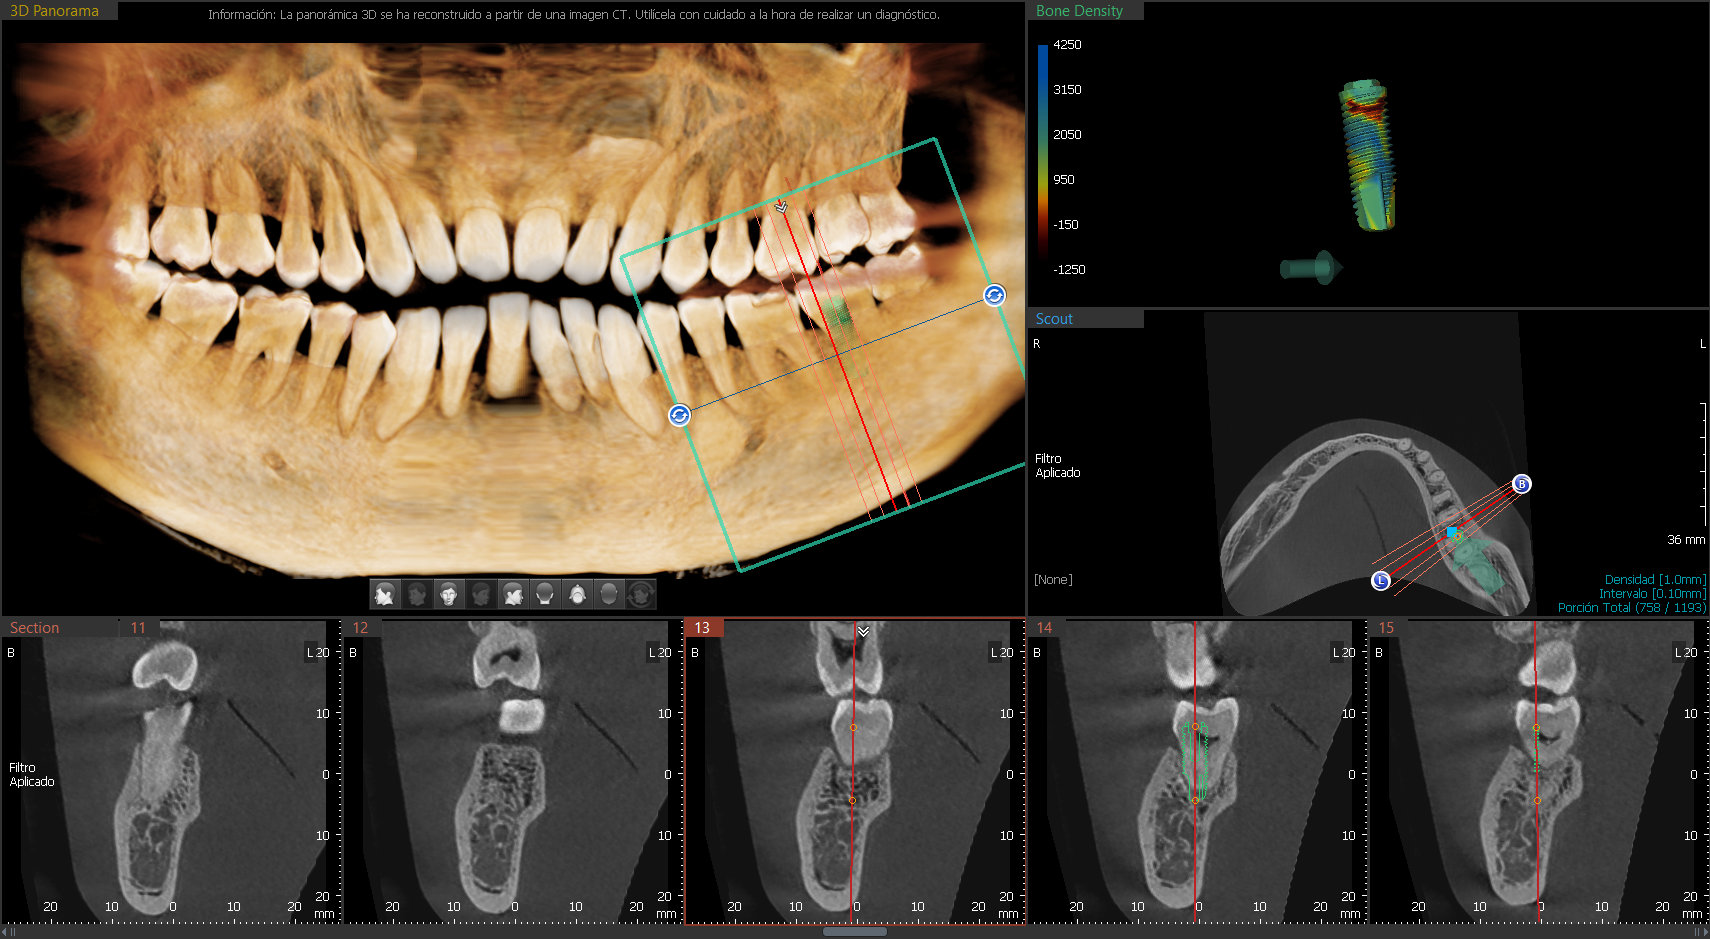

A9 cuenta con una tecnología lite que además de la función PANO + CEPH te permite obtener imágenes CT de manera lite para tu diagnóstico. Proporciona las imágenes más precisas y de mayor calidad.

Las imágenes 3D permiten realizar diagnósticos precisos para planificar los tratamientos dentales. Incluye la áreas maxilar y mandibular en una sola exposición. Ideal para cirugías de implantes y diagnósticos en cirugía oral.